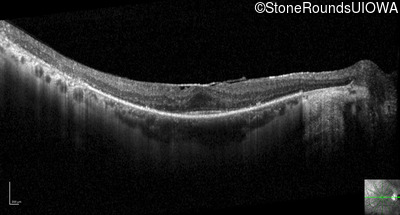

Optical Coherence Tomography - Left - 20/25 sc

Exemplar / OCT Stack

OCT Stack